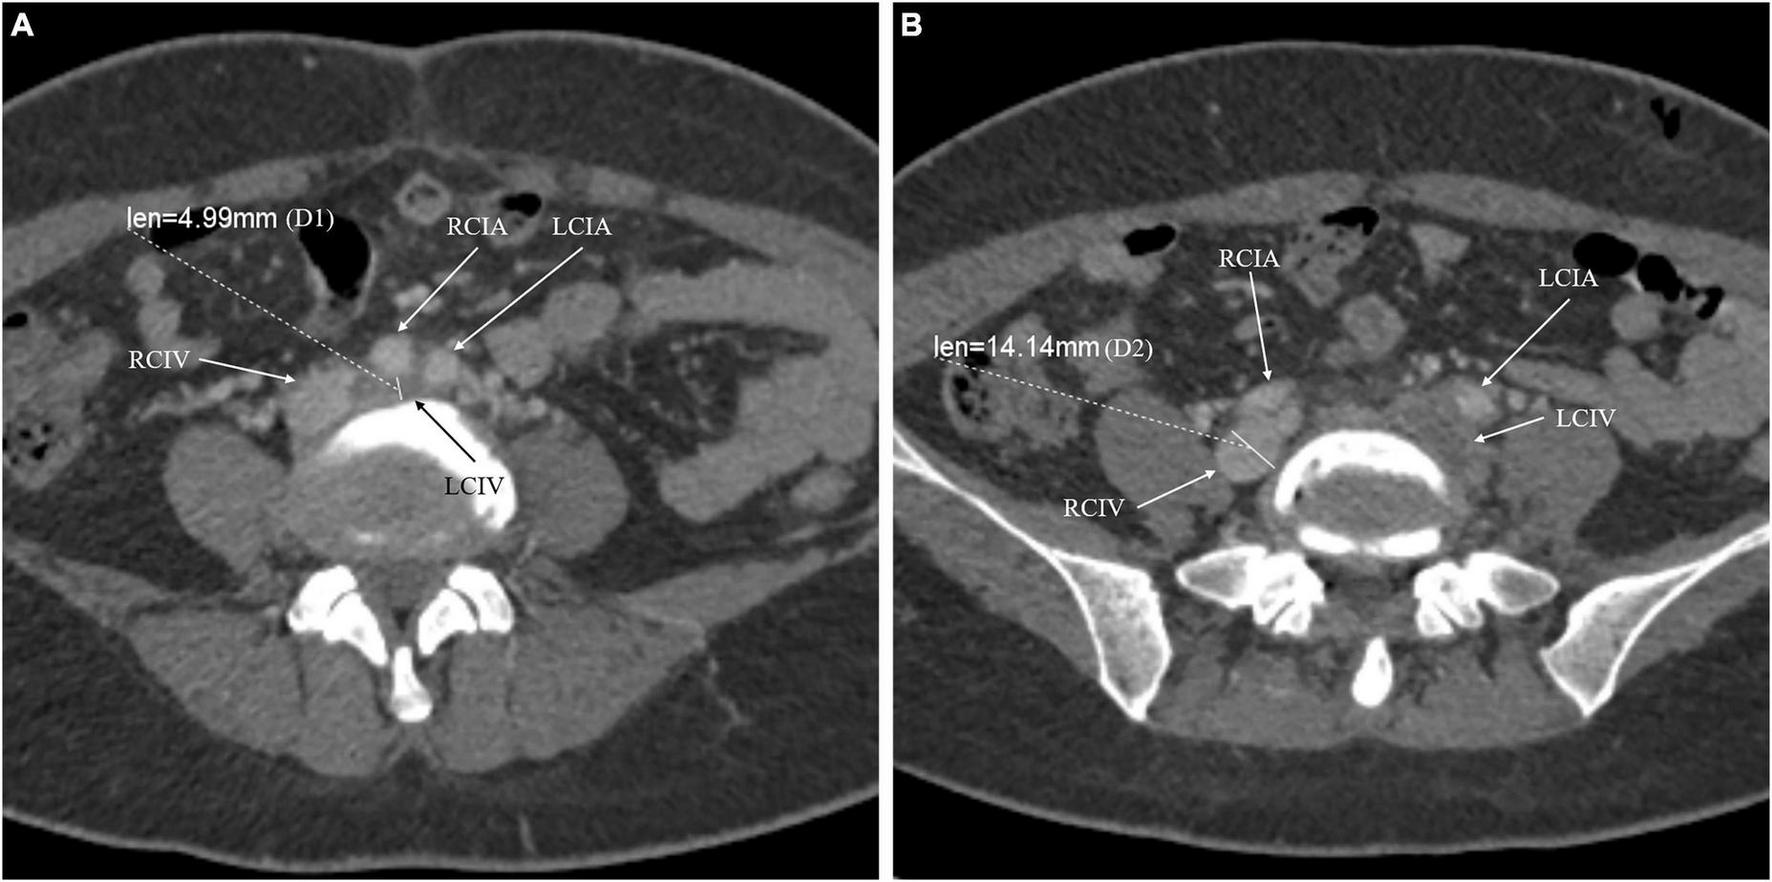

Left CIV compression was evaluated using quantitative and qualitative measures based on CTV. Adequate axial images were obtained, and the maximum CIV compression point was identified. The compression percentage was calculated using the formula (1 − D1/D2) × 100%, where D1 is the minimum diameter at the point of maximum compression, and D2 is the minimum diameter at the CIV caudal to the compression (16). For patients with left CIV thrombosis, we used the right distal CIV diameter as the reference denominator (Figure 1) (16). The qualitative estimate of CIV compression was performed according to the calculated compression percentage. The compression degree was classified into significant (compression percentage >50%) and non-significant (compression percentage ≤50%) (17).

FIGURE 1

The compression percentage of the common iliac vein was calculated using the following formula: (1 – D1/D2) × 100%. D1 is the minimum diameter at the point of maximum compression (A). Because the left common iliac vein was involved, D2 is the minimum diameter at the right common iliac vein caudal to the compression (B). For instance, the compression percentage of LCIV for the presented patient was: (1 – 4.99/14.14) × 100% = 64.7%. RCIV, right common iliac vein; RCIA, right common iliac artery; LCIV, left common iliac vein; LCIA, left common iliac artery.